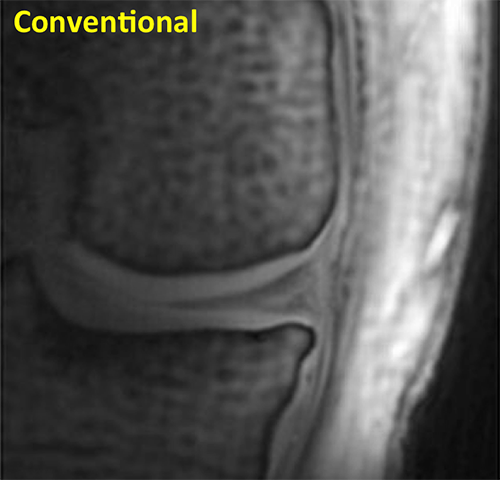

Knee Conventional

This conventional MRI of a knee shows articular cartilage with uniform signal intensity.